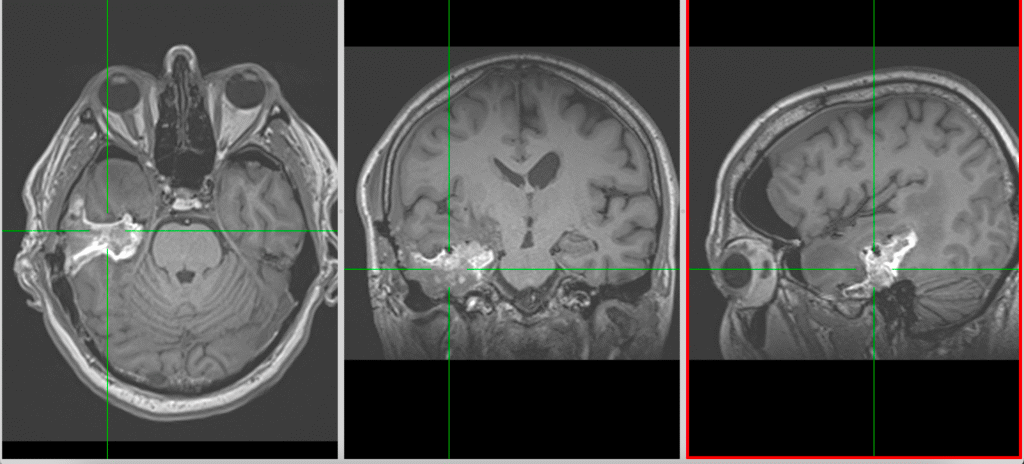

La nivel imagistic, glioblastomul apare adesea ca o leziune relativ bine delimitată, cu captare inelară de contrast și necroză centrală. Pentru ochiul neavizat, aceasta poate sugera o tumoră care ar putea fi „scoasă complet”. În realitate, ceea ce vedem pe RMN reprezintă doar componenta cea mai densă tumoral.

Imagistica – instrument esențial, dar imperfect

RMN-ul cerebral este standardul diagnostic, dar trebuie interpretat în context.

Pe lângă secvențele convenționale, tehnicile avansate aduc informații suplimentare:

- perfuzia evidențiază angiogeneza tumorală

- spectroscopia reflectă metabolismul celular

- DTI (tractografia) arată relația cu tracturile din substanța albă

Cu toate acestea, niciuna dintre aceste metode nu poate delimita complet infiltrarea microscopică. De aceea, planificarea chirurgicală și terapeutică trebuie să țină cont de această limitare.